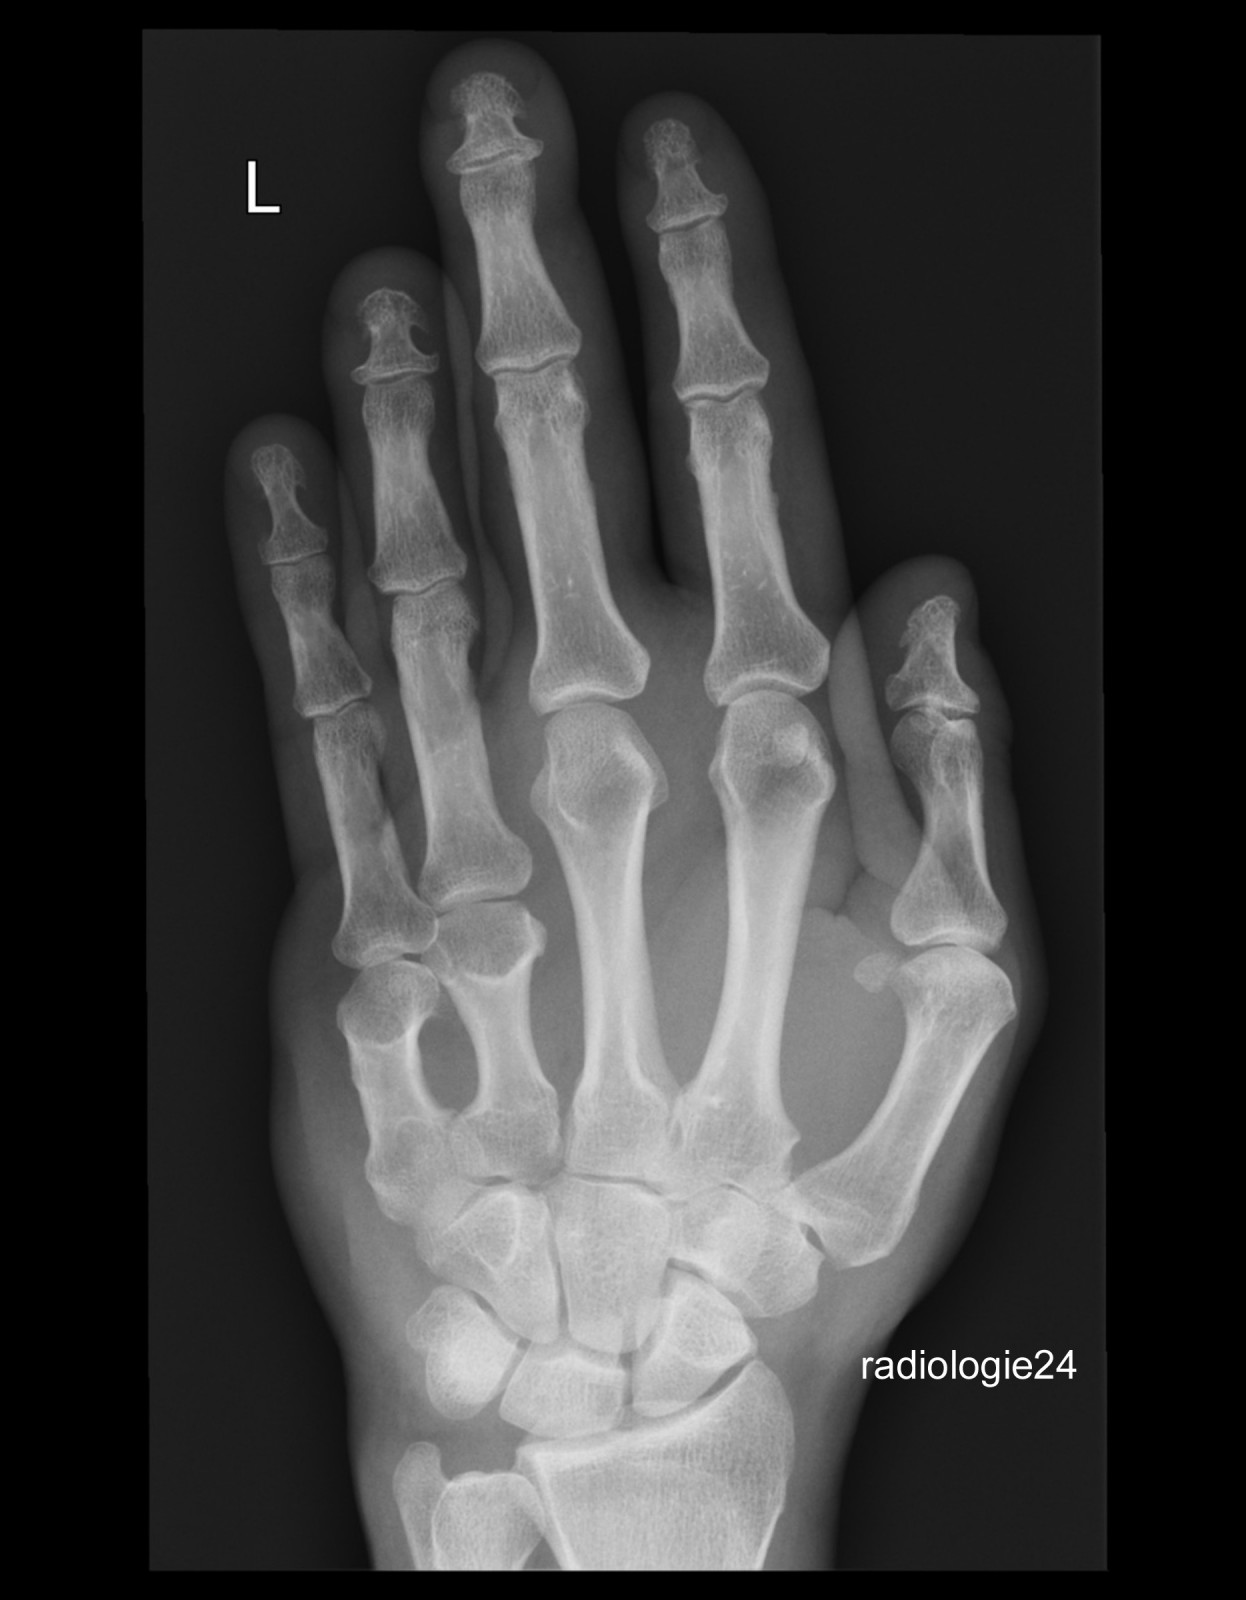

Röntgenfall des Monats Juni 2018 mit Auflösung

45 jähriger Patient Z.n. Sturz. Schmerzen Metacarpalia II/III. Fraktur? Ihre Diagnose?